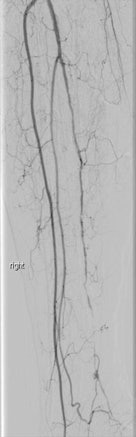

In endovascular treatment at the clinic, the prime goal is re-establishment of perfusion to relieve from rest pain, achieve healing of ulcers and gangrene, achieve limb salvage, and improve quality of life.

"The aim of revascularization is to restore direct pulsatile flow to at least one of the foot arteries, preferably the artery which supplies the anatomical region of the wound," he said. "The restoration of oxygenated blood may be important even when a primary amputation is planned to facilitate wound healing at the amputation site and to potentially lessen the extent of amputation and avoid a second one."